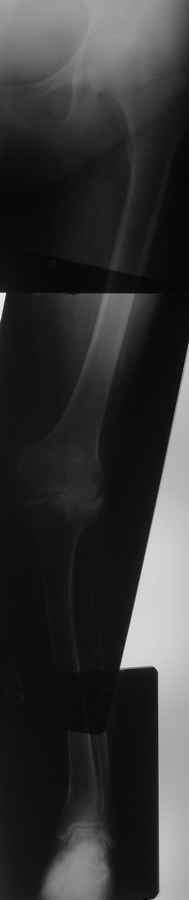

Уважаемые коллеги, интересует мнение специалистов по следующему случаю. Пациентка 56 лет,

поступила в отделение для эндопротезирования коленного сустава.9 лет больна ревматоидным

артритом.Во вложении осевой снимок конечности, после анализа которого в отделении

возникла дискуссия.Как поступить-сразу пойти на TKR или сначала выполнить коррекцию оси

голени? Если предпочесть эндопротезирование,то каких трудностей ожидать и какой системой

воспользоваться(Скорпио или LCS)? А может выполнить протезирование под контролем

навигации? Будут интересны любые мнения и замечания.Заранее спасибо всем откликнувшимся.